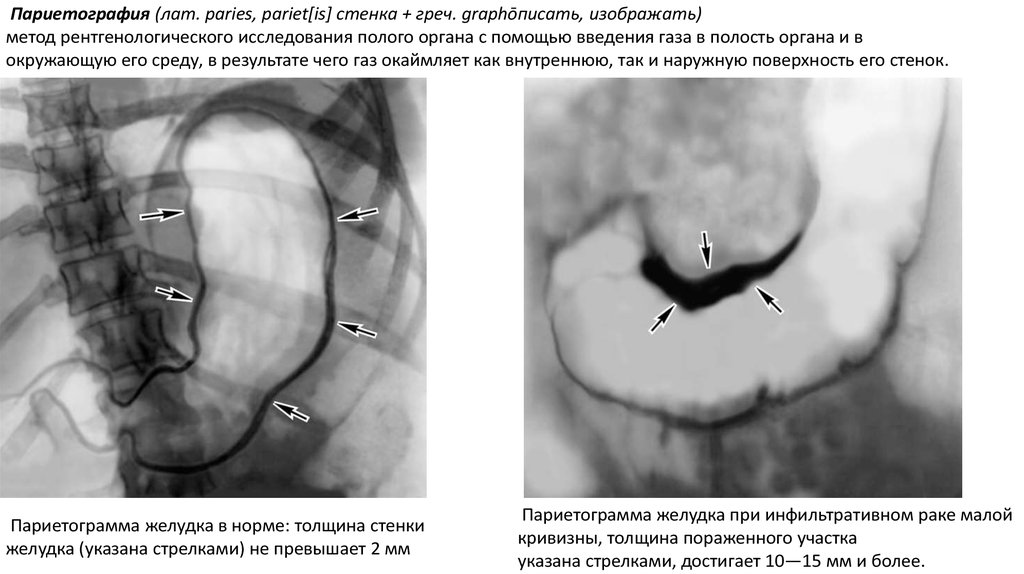

Париетография (лат. paries, pariet[is] стенка + греч. graphōписать, изображать)

метод рентгенологического исследования полого органа с помощью введения газа в полость органа и в

окружающую его среду, в результате чего газ окаймляет как внутреннюю, так и наружную поверхность его стенок.

Париетограмма желудка в норме: толщина стенки

желудка (указана стрелками) не превышает 2 мм

Париетограмма желудка при инфильтративном раке малой

кривизны, толщина пораженного участка

указана стрелками, достигает 10—15 мм и более.